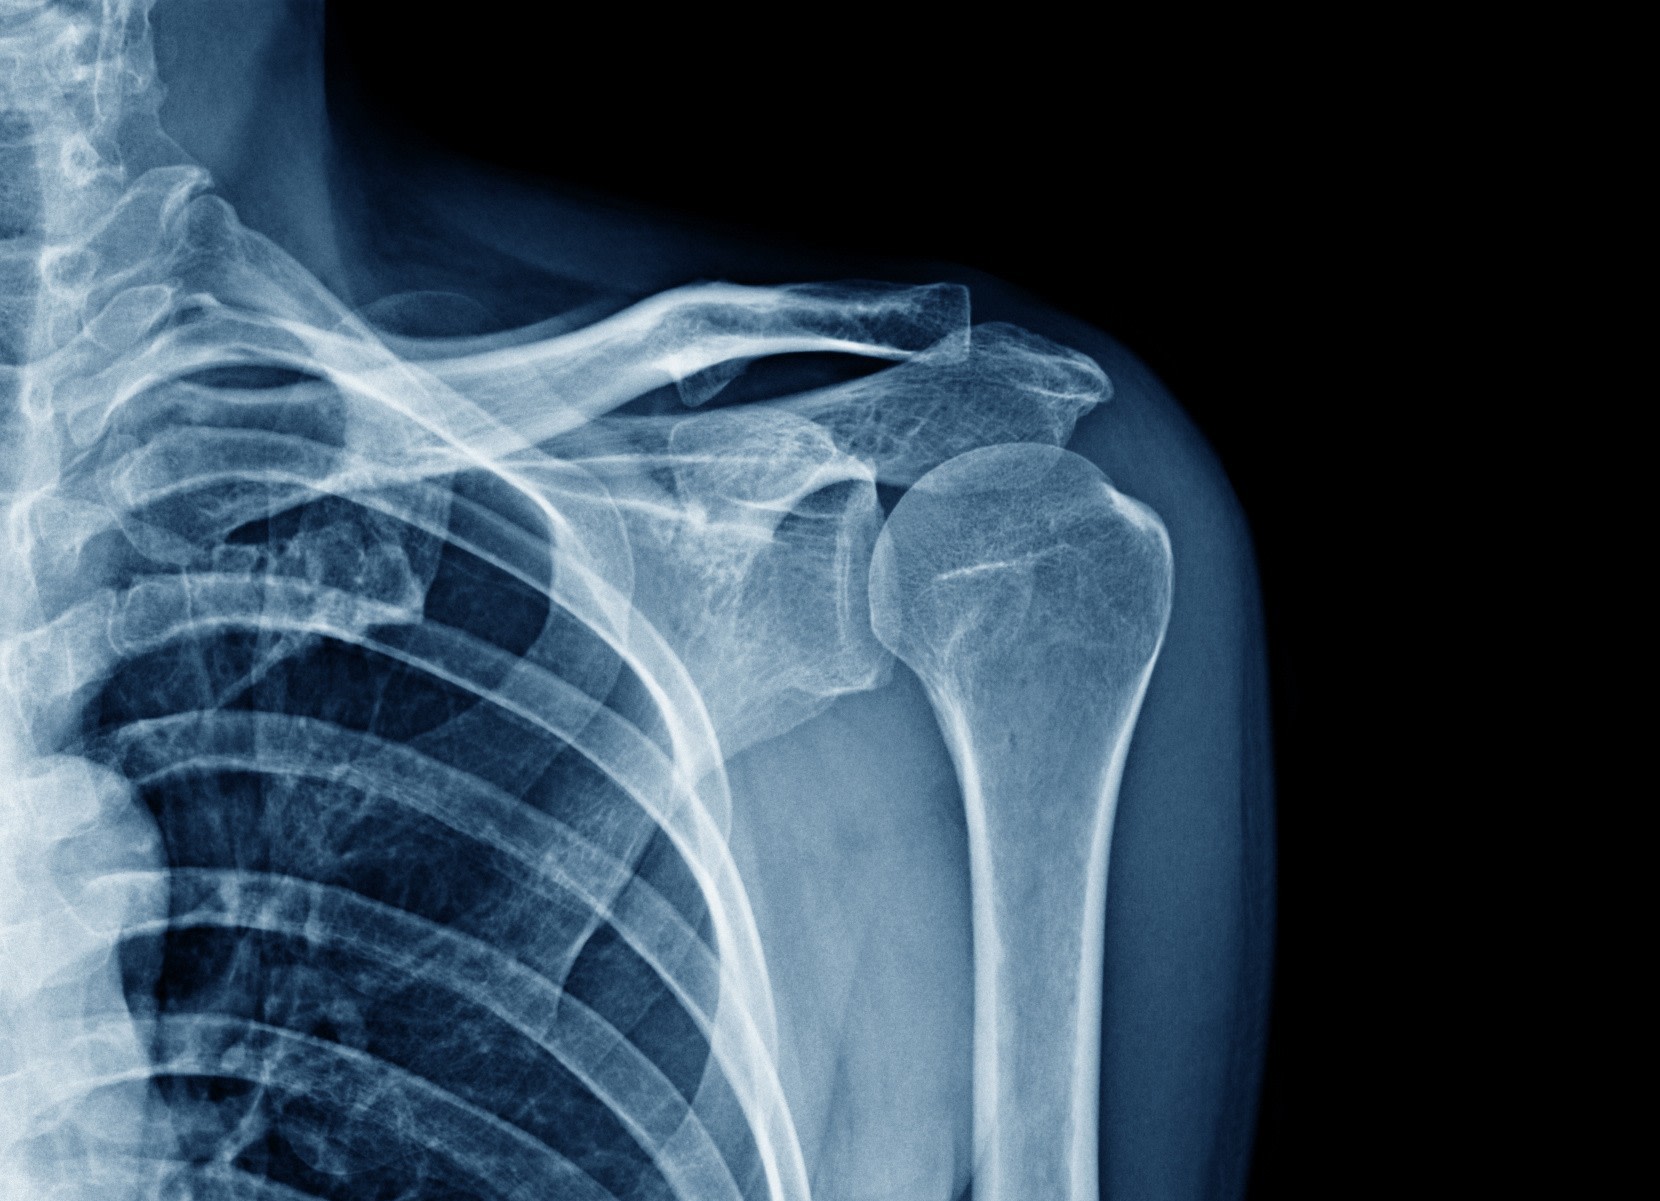

Capsulite ou épaule gelée